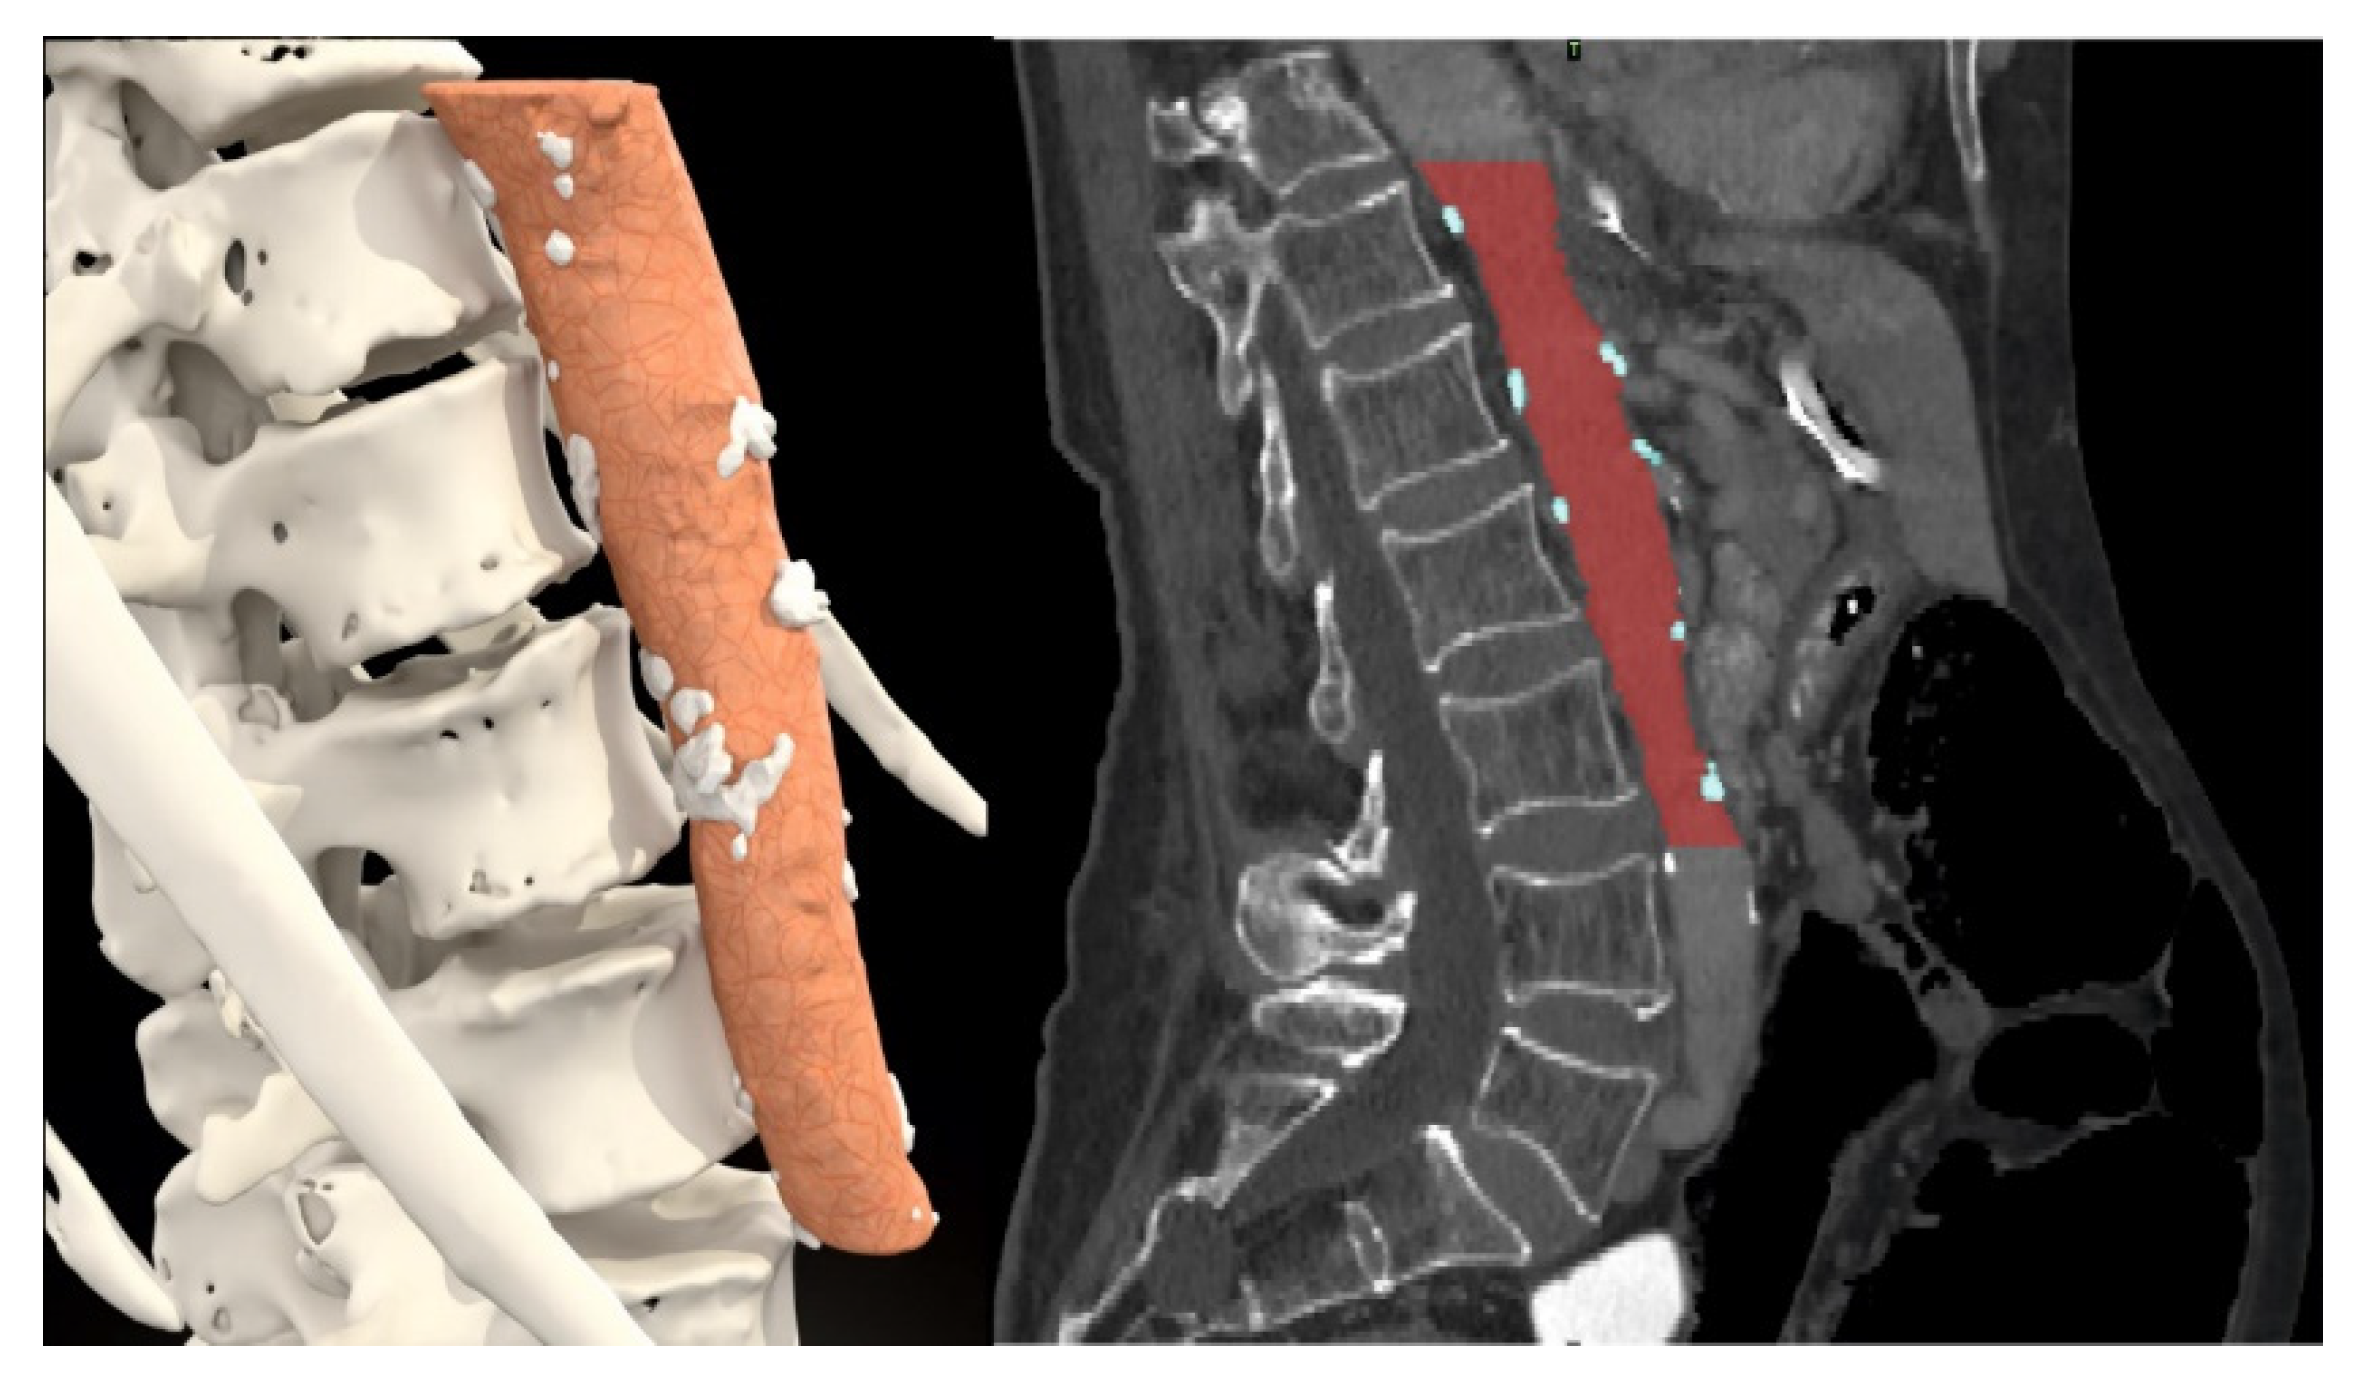

| Median percent of atherosclerotic plaques in aorta volume (IQR) (%) | 0.86 (0–3.81) | 0.60 (0–2.91) | 3.69 (1.87–8.24) | <0.001 |

| Number of patients with percent of calcification plaques in aorta volume under cut-off point | 100 (38.3%) | 66 (30.7%) | 34 (73.9%) | <0.001 |